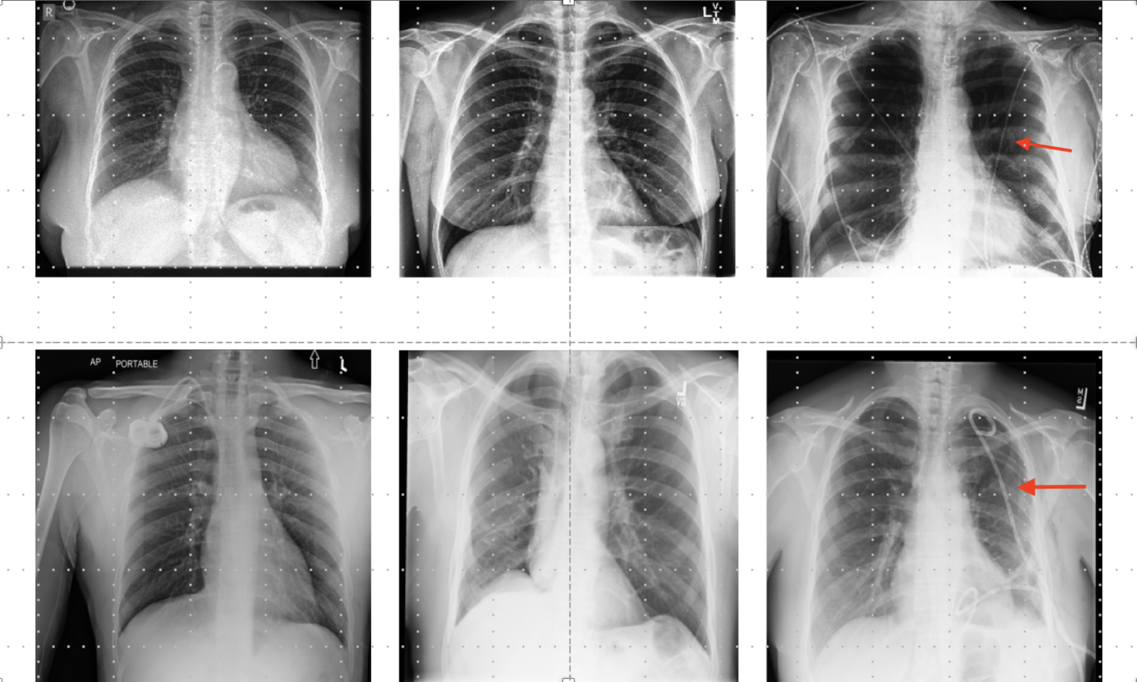

During my PhD at UPF, I investigated training sample strategies, addressing common challenges in medical imaging such limited data, class-imbalance, and noisy labels. I developed curriculum learning strategies that leveraged prior clinical knowledge from medical guidelines or estimated model uncertainty. In my postdoctoral research at ITU, I investigated transfer learning, with an emphasis on identifying proper pre-training sources and evaluating transferability metrics to improve model robustness. I also gained experience in conducting fairness analysis and critical data studies approaching these topics from a socio-technical perspective.

• Cathrine Damgaard & Trine Naja Eriksen (ITU) - Annotation Label Reliability, Drain and Pathology Detection in Publicly Available Chest X-ray Datasets (Research Project + Master Thesis)